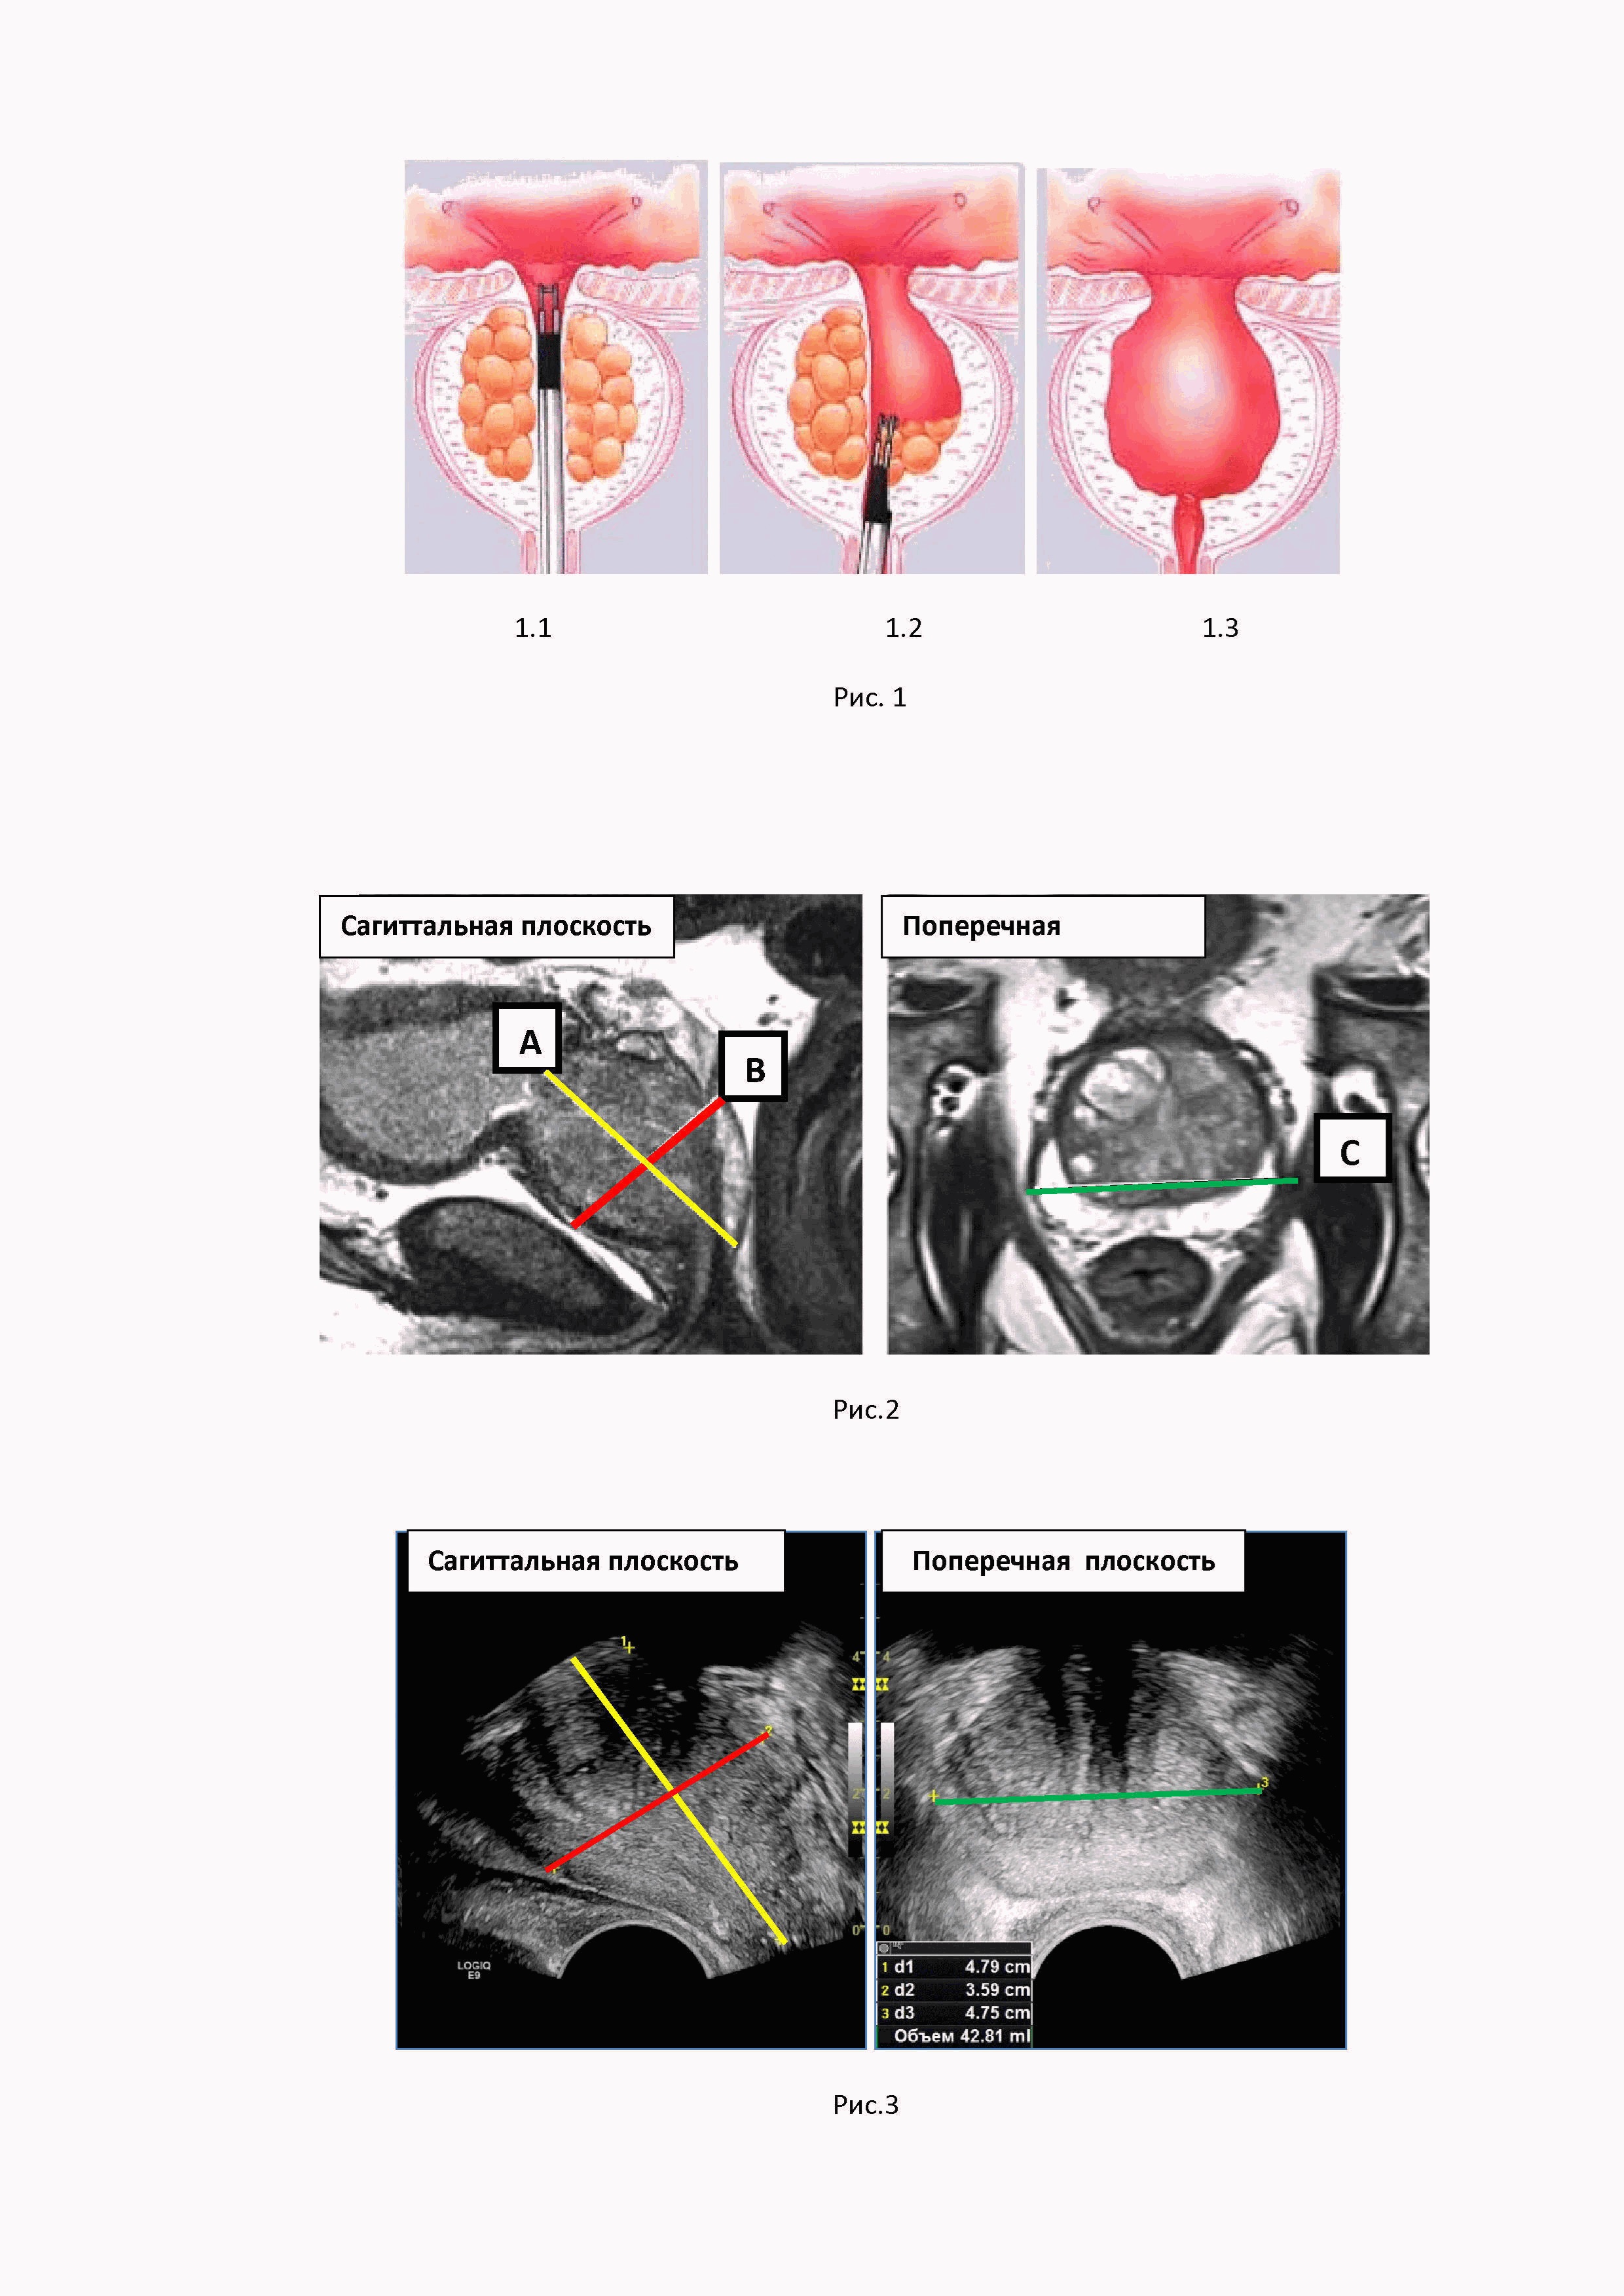

Изобретение относится к области медицины, в частности к ультразвуковой диагностике, и предназначено для улучшения количественной оценки остаточного объема ткани предстательной железы после ее резекции. Способ обеспечивает получение количественных показателей остаточного объема ткани резецированной простаты, что позволит вычислять плотность ПСА, значение которого в настоящее время расцениваются как один из надежных предикторов ранней диагностики рака простаты при динамическом наблюдении за больным. Точность измерения объема предстательной железы (простаты) приобрела принципиальную важность благодаря результатам последних исследований, в ходе которых было установлено, что наибольшей корреляцией среди лабораторных показателей и вероятностью рака простаты обладает показатель плотности ПСА (10, 12). Плотность ПСА рассчитывается как отношение значения исходной концентрации сывороточного общего ПСА к объему предстательной железы (2, 11, 13), а именно: где ПСА-D – плотность ПСА (от английского «PSA density»), На сегодняшний день именно плотность ПСА признается большинством экспертов одним из самых надежных прогностических критериев диагностики рака предстательной железы (РПЖ). При этом пороговым значением ПСА-D считается уровень 0,151 нг / мл / см3 (5). Однако у большой части мужчин старшей возрастной группы предстательная железа увеличивается в размерах, что требует хирургического лечения. Патологоанатомические изменения преимущественно наблюдаются в центральных отделах простаты, где формируется аденоматозная трансформация ткани (гиперпазия простаты, или аденома простаты). Аденоматозная ткань занимает центральную часть предстательной железы и деформирует шейку мочевого пузыря. Это приводит к формированию клинических проявлений аденомы простаты – дизурических жалоб и, что самое главное, к формированию нарушения опорожнения мочевого пузыря, которое, в конечном итоге, может стать причиной развития уремии. Исторически известен метод хирургического лечения данного состояния – чрезпузырная аденомэктомия по Федорову–Фрейеру. Аденомэктомия по Федорову-Фрейеру, несмотря на множество других предложенных методов лечения, относится к основным и наиболее радикальным методам лечения аденомы предстательной железы (1, 8). Несмотря на многочисленные модификации, техника данного оперативного вмешательства остается прежней (7, 9). При операции Федорова-Фрейера аденоматозные ткани удаляются вместе с пузырно-уретральным сегментом и предстательным отделом уретры одним блоком. В ходе операции образуется свободная полость в центральной части простаты, так называемый предпузырь, и его объем соответствует массе удаленных тканей простаты. При этом образуется тканевой дефект, соответствующий по форме эллипсу, диаметром от 3 см, а иссеченный край мочевого пузыря является границей его ложа. Боковыми и задней стенками служат остаточные ткани простаты, нижняя граница предпузыря располагается на уровне семенного бугорка (6). Проблема определения остаточного объема резецированной предстательной железы связана с отсутствием объективной формулы для подсчета объема железы в послеоперационном периоде по причине изменения ее конфигурации после хирургического лечения. На рис.1 представлены этапы трансуретральной резекции центральной части простаты (аденомэктомии): 1.1. Резектоскоп введен в уретру. 1.2. Этап удаления аденоматозной ткани в центральной части простаты. 1.3. Завершение операции с формированием остаточной полости (предпузыря) и сохранением периферической части простаты. Имеющиеся формулы подсчета объема неоперированной железы подразумевают форму простаты, близкую к объемному эллипсу. После проведения резекции конфигурация простаты меняется за счет удаления ткани в ее центральных отделах и формирования предпузыря округлой формы, что не позволяет объективно измерить объем органа. Известный способ определения объема простаты с использованием ультразвуковой диагностики (4) и МРТ (3, 5). При проведении магнитно-резонансной томографии малого таза определение размеров предстательной железы является необходимым условием, помимо указания её размеров современные тенденции требуют и определения объёма простаты. Для определения размеров железы используются Т2-взвешенные изображения (Т2-ВИ), за счёт высокой контрастности полученных изображений, что позволяет чётко дифференцировать анатомические границы железы (3). Измерения производят в двух взаимно перпендикулярных плоскостях: сагиттальной и аксиальной (или поперечной) (рис.2). Границы и срезы выбираются в каждом случае врачом-рентгенологом индивидуально в зависимости от формы железы, её анатомических особенностей, выраженности гиперпластических изменений в транзиторной зоне. В сагиттальной плоскости от основания до апекса простаты измеряются ее продольной размер (А), в средней трети железы измеряются передне-задний размер железы (В), а поперечной плоскости измеряют ширину простаты (С). Согласно рекомендациям PI-RADS v2.1, измерение объема предстательной железы ПЖ проводится вручную на основе формулы объема эллипсоида или с помощью автоматических алгоритмов измерения объема (5). V простаты =А х В х С х 0.523, где А – продольный размер, В – переднезадний размер, С – ширина простаты, 0.523 – поправочный коэффициент для вычисления объема эллипсоида. Использование единого подхода к расчету объема предстательной железы с помощью формулы объема эллипсоида имеет особое значение. В PI-RADS v2.1 рекомендуют измерение максимального переднезаднего размера и перпендикулярного к нему продольного размера на срединных сагиттальных T2-ВИ, а максимальную ширину рекомендуют измерять на поперечных срезах в T2-ВИ (5). При проведении УЗИ простаты с целью измерения объема ПЖ также традиционно используют формулу измерения объема эллипсоида (4) V простаты =А х В х С х 0,523, где А – продольный размер простаты, В – передне-задний размер, С – ширина простаты в средней трети, 0.523 – поправочный коэффициент (14). Ультразвуковое исследование проводят в двух взаимоперпендикулярных плоскостях – сагиттальной и поперечной. В саггитальной плоскости измеряют продольный размер простаты от основания простаты до апекса железы (А), в этой же плоскости перпендикулярно продольному размеру в средней трети железы измеряют передне-задний размер (В). Далее перемещают датчик в поперечную плоскость и в средней части железы производят измерение ширины железы С, проводя измерительную дистанцию от боковых границ органа. На рис.3 представлен алгоритм измерения объема неоперированной простаты при проведении трансректального УЗИ в двух плоскостях сагиттальной и поперечной. В сагиттальной плоскости сканирования от основания до апекса железы желтым пунктиром обозначен продольный размер (А). В этой же плоскости красный пунктир, проведенный от передней границы до задней границы железы, соответствует передне-заднему размеру. В поперечной плоскости сканирования зеленый пунктир, проведенный от правой боковой до левой боковой границы простаты, соответствует ширине железы (С) в средней трети железы. После проведения резекции при хирургическом лечении аденомы простаты конфигурация простаты меняется за счет удаления ткани в ее центральных отделах, поскольку на месте удаленной ткани в центральных части железы формируется предпузырь округлой формы, что не позволяет объективно измерить объем органа. На рис.4 представлено ультразвуковое изображение, демонстрирующее остаточный, объем резецированной простаты и изменение конфигурации железы за счет формирования предпузыря на месте удаленной аденоматозной ткани (объем предпузыря обозначен белой стрелкой). Указаний на необходимость измерения предпузыря после резекции простаты методом УЗД или МРТ в доступной литературе нам не встретилось. В руководстве «Магнитно-резонансная томография предстательной железы» под ред. А.В. Мищенко дается описательная характеристика предпузыря как воронкообразного дефекта аденоматозно-измененной простаты без метрических показателей (3). В тоже время точность измерения объема приобрела принципиальную важность в последние годы благодаря результатам последних исследований, в которых была продемонстрирована значимость критерия плотности ПСА в сыворотке крови (в нг/мл), рассчитываемой как соотношение сывороточного ПСА к объему предстательной железы (11,13). На сегодняшний день именно плотность ПСА признается большинством экспертов одним из самых надежных прогностических критериев диагностики РПЖ. Технической проблемой, на решение которой направлено изобретение является разработка достоверного и простого способа определения остаточного объема резецированной простаты после аденомэктомии. Техническим результатом разработанного способа является объективизация значения остаточного объема резецированной простаты, что позволит корректно измерять плотность ПСА в остаточном объеме резецированного органа по формуле (11,13) где ПСА-D – плотность ПСА (от английского «PSA density»), Способ определения остаточного объема резецированной простаты характеризуется тем, что проводят трансректальное ультразвуковое исследование простаты, при котором последовательно производится измерение простаты целиком с целью определения объема железы, включая объем предпузыря, на следующем этапе проводят измерение и вычисление объема предпузыря, и, путем вычитания объема предпузыря из объема простаты, измеренного целиком, получают остаточный объем резецированной простаты. При осуществлении способа проводят трансректальное исследование. С этой целью микроконвексный ультразвуковой датчик частотой 7 – 9 МГц вводят в ампулу прямой кишки, предварительно изолировав его поверхность резиновым ультразвуковым наконечником для соблюдения асептики. Проводят детальную оценку предстательной железы и предпузыря. Далее приступают к проведению измерения простаты и предпузыря с целью получения показателей объема обеих структур. Измерение объема резецированной простаты целиком получают при измерении трех линейных параметров – продольного (А), передне-заднего (В) размеров и ширины ПЖ(С). На рис.5.1 представлено измерение объема резецированной простаты целиком, включая объем предпузыря. Измерение размеров производится последовательно в сагиттальной и поперечной плоскостях сканирования. В сагиттальной плоскости (левое фото) проводится желтый пунктир от границы предпузыря (белый пунктир) до апекса простаты. Граница предпузыря маркируется виртуальной замыкающей линией, от которой измерительный маркер направляется к верхушке простаты. Данный размер соответствует продольному размеру простаты А. Желтый пунктир, соответствующий передне-заднему размеру железы (В), проводится в этой же плоскости от передней к задней границе простаты. Далее измерение производится в поперечной плоскости сканирования простаты, для чего датчик размещают перпендикулярно первоначальной дистанции. В поперечной плоскости (правое фото) зеленый пунктир, проведенный от боковых границ железы, соответствует ширине простаты в средней трети железы (С). Измерение ширина простаты производят на уровне средней части простаты. На основании полученных показателей по известной формуле (4) вычисляют объем простаты вместе с предпузырем (целиком): Vпростаты целиком = А х В х С х 0,523, где А – продольный размер простаты, см, В – передне-задний размер простаты, см, С – ширина простаты, см, 0.523 – поправочный коэффициент. Второй этап. Далее приступают к измерению объема полости предпузыря. Для этого проводят линейные измерения в двух плоскостях – сагиттальной и поперечной - и получают значения продольного (a), передне-заднего (b) размеров и ширины (c) предпузыря. Продольный размер измеряют в сагиттальной плоскости, проводя измерительный маркер от замыкающей верхние границы предпузыря виртуальной линии до нижней границы предпузыря с простатой на уровне семенного бугорка. В этой же плоскости сканирования измеряют передне-задний размер предпузыря, для чего перпендикулярно к первой линии проводят измерительный маркер спереди назад по передне-задним границам предпузыря в его средней трети. Ширина предпузыря изменяется в средней части объекта в поперечной плоскости сканирования железы. На рисунке 5.2 представлено измерение объема предпузыря. От верхней границы предпузыря (белая пунктирная линия – виртуальная граница простаты в зоне резекции) проводится сплошная желтая линия до нижней границы предпузыря, что соответствует продольному размеру. Красная сплошная линия, проведенная также в сагиттальной плоскости, от передней до задней границы полости предпузыря, соответствует передне-заднему размеру. Далее датчик располагают в перпендикулярной плоскости сканирования, и получают изображение железы в поперечной плоскости. Сплошная зеленая линия, проведенная от боковых границ полости предпузыря, соответствует его ширине. На основании полученных показателей вычисляют объем предпузыря по формуле вычисления объема эллипсоида (4): Vпредпузыря = a х b х c х 0,523, где а – продольный размер предпузыря, b – передне-задний размер предпузыря, с – ширина предпузыря, 0.523 – поправочный коэффициент. Третий этап. Вычисление остаточного объема резецированной простаты. На основании проведенных измерений вычисляют остаточный объем резецированной простаты (V резецированной простаты) Vрезецированной простаты = Vпростаты целиком –Vпредпузыря или Vрезецированной простаты = (А х В х С х 0,523)– a х b х c х 0,523) Полученная величина является основой для измерения плотности ПСА-D (11,13), измерение которой проводиться по известной формуле где ПСА-D – плотность ПСА, нг/мл/см³, ПСА общ. – значения общего ПСА, нг/мл, Vост. – остаточный объем резецированной простаты, см3. Установление количественных показателей остаточного объема ткани резецированной простаты позволяет вычислять плотность ПСА. Значение плотности ПСА получают как соотношение показателя ПСА в нг/мл к объему остаточной ткани резецированной простаты в куб.см. Значение плотности ПСА в настоящее время рассматривается как важнейший фактор при динамическом наблюдении пациентов при онконасторженности (5). При получение значений ПСА-D более 0.151 пациент должен рассматриваться как потенциальный больной раком простаты с проведением стандартизированного онкологического исследования (МКБ Z03.1 Наблюдение пациента с подозрением на злокачественное новообразование). В связи с этим количественная оценка остаточного объема резецированной простаты является важнейшим условием выбора тактики ведения больного. Невозможность провести объективное измерение объема простаты после резекции традиционным способом связано с существенным изменением формы железы после операции, что не позволяет использовать в клинической практике показатель «плотность ПСА», важность которого доказана в онкоурологии. Невозможность использования в клинической практике достоверного показателя уровня плотности ПСА может привести к ложному представлению о состояния больного и выбору ошибочной тактики. Клинические примеры: №1 Больной П., 65 лет. Наблюдается урологом. Пять лет назад перенес резекцию простаты (трансуретральную аденомэктомию). ПСА в динамике 1.3 нг/мл - 2.2 нг/мл - 1.8 нг/мл. В настоящий момент ПСА 5.21 нг/мл. Жалоб активно не предъявляет. Результаты УЗИ: рис. 6.1. На первом этапе в сагиттальной плоскости измеряли объем простаты (вместе с предпузырем), для чего в сагиттальной плоскости от виртуальной границы зоны резекции мочевого пузыря (белый пунктир) проводили измерительную дистанцию до верхушки простаты (дистанция обозначена желтым пунктиром) и получили значение 4.2 см. Далее в этой же плоскости сканирования средней трети простаты проводили измерительную дистанцию перпендикулярно первому измерению от передней до задней границы железы (дистанция обозначена красным пунктиром) с получением результата 4.2 см. Далее переходили в поперечную плоскость сканирования простаты, для чего разворачивали датчик перпендикулярно предыдущему положению. Измерение ширины простаты (дистанция обозначена зеленым пунктиром) проводили от правой до левой границы простаты в средней ее трети с получением результата 5.2 см. Далее производили вычисление объема простаты целиком с объемом предпузыря по известной формуле вычисления объема эллипсоида: V простаты целиком = 4.2 х 4.2 х 5.2 х 0.523 = 47.9 см3. Измерение объема предпузыря (рис.6.2) производили в двух плоскостях - сагиттальной и поперечной. Длинник измеряли в сагиттальной плоскости от виртуальной границы предпузыря с мочевым пузырем (белый пунктир) до нижней границы (желтая сплошная линия) с получением результата 2.4 см. В это же плоскости сканирования получали передне-задний размер предпузыря, проводя линию в средней части предпузыря от передней до задней его границы (красная сплошная линия) с получением результата 2.3 см. Измерение ширины предпузыря проводили в поперечной плоскости сканирования, изменив положение датчика на перпендикулярное начальному и проводя измерительный маркер от правой до левой границы предпузыря (зеленая сплошная линия) с получением результата 2.3 см. Далее вычисляли объем предпузыря по известной формуле объема эллипсоида: Vпредпузыря = 2.4 х 2.3 х 2.3 х 0.523= 6.6 см3. Остаточный объем резецированной простаты вычисляли путем вычитания объема предпузыря из объема простаты целиком с получением результата: Vрезецированной простаты =Vпростаты целиком –Vпредпузыря = 47.9 –6.6= 41.3 см3. Плотность ПСА (ПСА-D) вычисляли путем деления показателя ПСАобщ. в нг/мл на остаточный объем резецированной простаты (Vрезецированной простаты) в куб. см: ПСА-D = 5.21 нг/мл : 41.3 см3 = 0.126 нг/мл/ см3. Поскольку полученные результаты плотности ПСА соответствуют нормальному значению (норма до 0.151), больному было предложено динамическое наблюдение, за время которого данных за онкологический процесс выявлено не было. № 2 Больной Л., 72 лет. Двенадцать лет назад перенес радикальную аденомэктомию по поводу гиперплазии простаты. Динамически не наблюдался. В настоящее время обратился к урологу по поводу жалоб на умеренную болезненность при мочеиспускании. ПСА 3.83 нг/мл. С целью выявления патологии простаты проведено УЗИ. Определяли объем простаты целиком. С этой целью при проведении трансректального УЗ-сканирования сагиттальной плоскости (рис.7.1) проводили измерительный маркер (желтый пунктир) от виртуальной границы предпузыря с мочевым пузырем (белый пунктир) до верхушки простаты, получив значения длинника простаты 3.5 см. В этой же плоскости проводили измерение передне-заднего размера простаты, для чего проводили измерительный маркер (красный пунктир) от передней до задней границы простаты в средней трети органа с получением результата 3.3 см. Для измерения ширины простаты переводили датчик в перпендикулярное положение, и в поперечной плоскости сканирования на уровне средней трети простаты проводили измерительный маркер (зеленый пунктир) от правой до левой границы железы, получив результат 5.0 см. Объем простаты целиком (вместе с предпузырем) вычисляли по известной формуле объема эллипсоида: V простаты целиком = 3.5 х 3.3 х 5.0 х 0.523 = 30.2 куб.см. Объем предпузыря вычисляли в двух плоскостях (рис.7.2): длинник предпузыря и передне-задний размер пузыря получали при сканировании в сагиттальной плоскости. Для получения размера длинника проводили измерительный маркер (желтая сплошная линия) от виртуальной границы предпузыря (белый пунктир) до проекции нижней границы предпузыря (проекция семенного бугорка) с получением размера 2.6 см. Далее измеряли переднее-задний размер предпузыря, для этого измерительный маркер (красная сплошная линия) проводили перпендикулярно первой дистанции в направлении от передней до задней границы предпузыря с получением результата 2.2 см. Следующим этапом сканирования было получение показателя ширины предпузыря в поперечной плоскости сканирования железы. Для этого измерительный маркер (зеленая сплошная линия) проводили в средней части простаты от правой до левой границы предпузыря с получением результата 2.3 см. Вычисление объема предпузыря проводили по формуле объема эллипсоида: Vпредпузыря = 2.6 х 2.2 х 2.3 х 0.523=6.9 куб.см. Вычисление остаточного объема резецированной простаты проводили путем вычитания объема предпузыря из объема простаты целиком. Vрезецированной простаты = Vпростаты целиком - Vпредпузыря = 30.2 – 6.9 = 23.3 см3. Плотность ПСА вычисляли путем деления показателя ПСАобщ. в нг/мл на остаточный объем резецированной простаты (Vрезецированной простаты): ПСА-D=3.83 нг/мл : 23.3 куб.см = 0.164 нг/мл/см3. Полученный результат превышал допустимое значение (норма до 0.151), и пациенту был поставлен диагноз: Z03.1. Наблюдение пациента с подозрением на злокачественное новообразование, что потребовало развернутого онкологического обследования - была проведена компрессионная соноэластография, в левой доле выявлен очаг высокой ригидности, что свидетельствует о наличии злокачественного процесса. Выполненная МРТ подтвердила наличие патологического очага левой доли резецированной простаты. Проведена трансректальная пункционная биопсия под УЗ-наведением. По данным биопсии: аденокарцинома, Gleason sum 3+3= 6. Больной направлен на консультацию к урологу-онкологу для выработки дальнейшей тактики лечения. Литература 1. Доброкачественная гиперплазия предстательной железы. Под ред. Н.А. Лопаткина. М., 1997. 2. Кнеев А.Ю., Школьник М.И., Богомолов О.А., Вершинская Ю.Г., Жаринов Г.М. Плотность простатспецифического антигена как прогностический маркер у больных локализованным раком предстательной железы. Урологические ведомости. 2021, Том 11, № 3, стр. 205-212. 3. Магнитно-резонансная томография предстательной железы / Дубицкий Д., Мищенко А. В., Л., Трофименко И. А. – Москва: ГОЭТАР-Медиа, 2021. - 528 с. 4. Назаренко Г.И., Хитрова А.Н. Ультразвуковая диагностика предстательной железы в современной урологической практике. – Москва: Издательский дом «Видар-М», 2012. – 288 с. 5. Рубцова Н. А., Мищенко А. В., Данилов В. В., Гулин Г. А., Алексеев Б. Я., Каприн А. Д. PI-RADS v2.1: движение на пути к ясности (комментарии к обновленной версии). Онкоурология, 2020, № 2, т.16, стр. 151-28. 6. Сергиенко Н.Ф., Василенко М.И., Кудряшов О.И. Классическому радикальному экстрауретральному способу аденомэктомии более 30 лет», Урология. 2015, № 4, стр.39-43. 7. Сергиенко Н.Ф., Василенко М.И., Кудряшов О.И. К вопросу о так называемом «золотом стандарте» оперативного лечения аденомы предстательной железы. Урология, 2021, № 4, стр. 69-72. 8. Степанов В.Н. Симптоматика и клиническое течение доброкачественной гиперплазии предстательной железы. В кн.: Доброкачественная гиперплазии предстательной железы. Под ред. Н.А. Лопаткина. М., 1997. С. 41–45. 9. Урология: учебник/ Б.К. Комяков. М.: ГОЭТАР-Медицина, 2011. – стр.309-317. 10. Dong F. et al. Validation of pretreatment nomograms for predicting indolent prostate cancer: efficacy in contemporary urological practice. J Urol 2008;180:150. 11. Lee S.J., Oh Y.T., Jung D.C. et al. Combined analysis of biparametric MRI and prostate-specific antigen density: role in the prebiopsy diagnosis of Gleason score 7 or greater prostate cancer. AJR Am J Roentgenol 2018;211(3):W166–72. DOI: 10.2214/AJR.17.19253. 12. Loeb S. et al. Active surveillance for prostate cancer: a systematic review of clinicopathologic variables and biomarkers for risk stratification. Eur Urol 2015;67:619. 13. Mehralivand S., Shih J.H., Rais-Bahrami S. et al. A magnetic resonance maging-based prediction model for prostate biopsy risk stratification. JAMA Oncol 2018;4(5):678–85. DOI: 10.1001/jamaoncol.2017.5667 14. Terris M.K., Stamey T.A. Detrmination of prostate volume by transrectal ultrasound. J.Urol.1991; 145 (5);984-987.